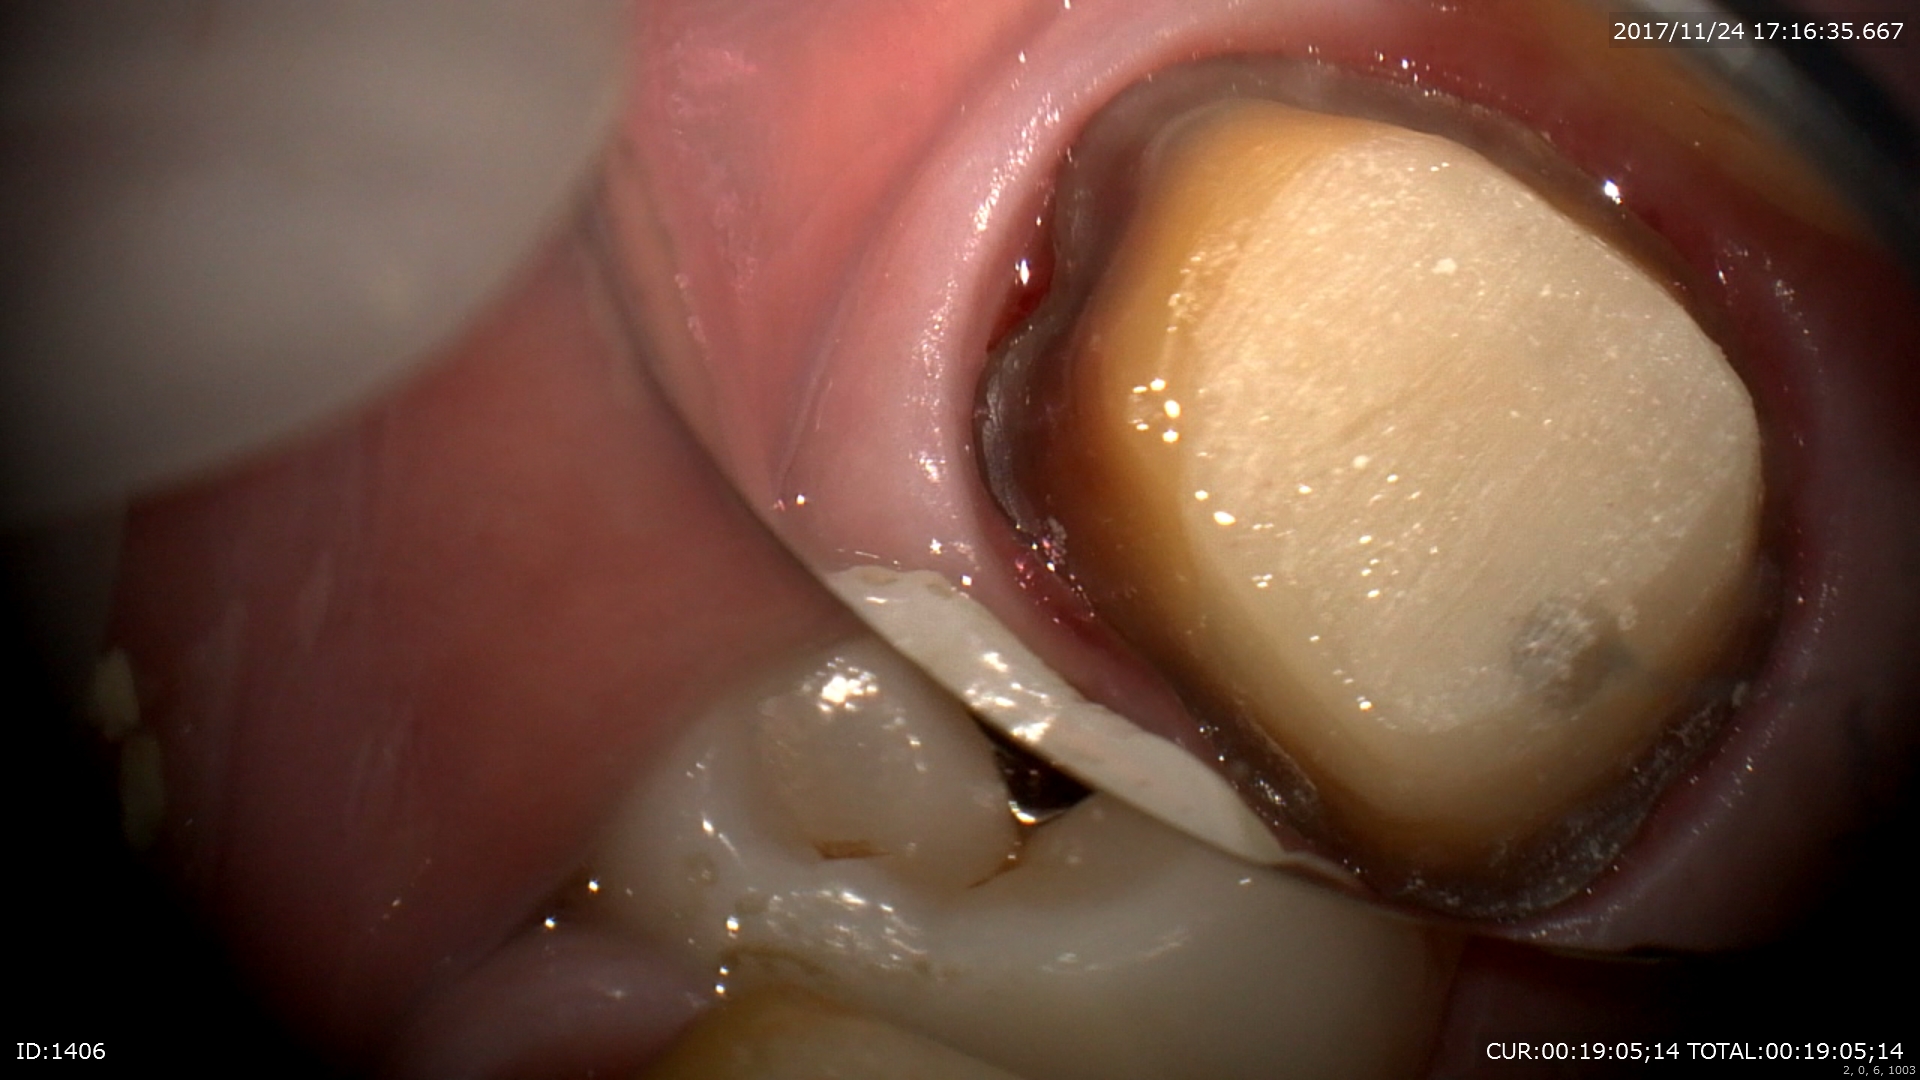

今年も早かったですねー。今年も顕微鏡治療の強化に数多くのセミナーやトレーニングに費やしました。年始から岡口先生や秋山先生のセミナーで顕微鏡の扱い方、アドバンスと非常に充実した1年でした。

2018年の「顕微鏡治療がもたらす恩恵」は今までの治療の質を大きく変え、患者さまの沢山の笑顔と安心を作りました。2019年も顕微鏡治療のさらなる強化、トレーニングを積み患者さまにお返ししたいと思います。

「1本でも多くの歯を保存する事」それが私の歯科医師としての使命。